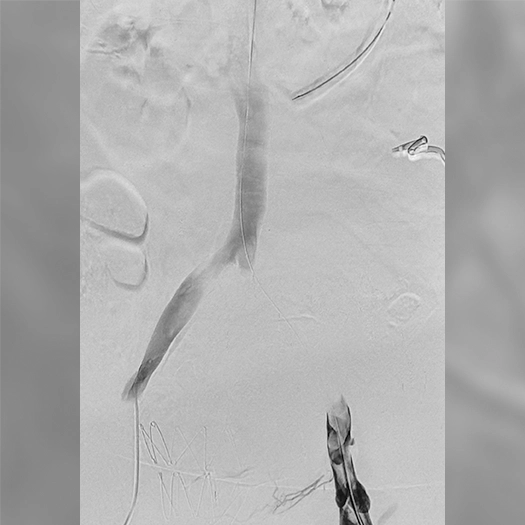

Pulmonary Embolism Cases

Venous Cases

Images used with permission and provided for illustrative purposes only. Procedural techniques and decisions based on physician’s medical judgment. Individual results may vary. Consents on file at Penumbra, Inc.